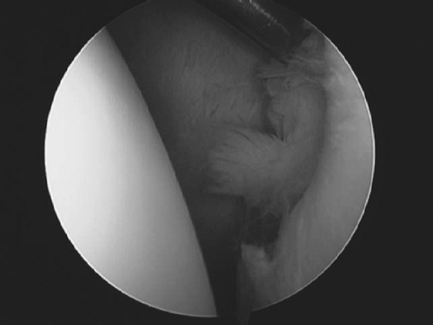

Figure 32-2 Arthroscopic picture of a Bankart injury viewed from the posterior portal (humeral head on the left and glenoid on the right).